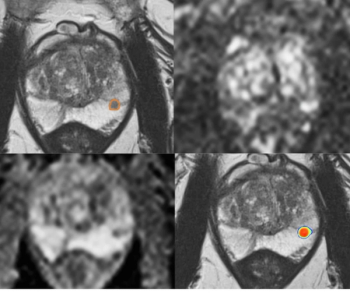

A model that combines MRI-based deep learning radiomics and clinical factors demonstrated an 84.8 percent ROC AUC and a 92.6 percent precision-recall AUC for predicting perineural invasion in prostate cancer cases.